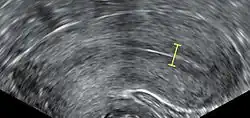

IVF may be used to overcome female infertility when it is due to problems with the fallopian tubes, making in vivo fertilisation difficult. It can also assist in male infertility, in those cases where there is a defect in sperm quality; in such situations intracytoplasmic sperm injection (ICSI) may be used, where a sperm cell is injected directly into the egg cell. This is used when sperm has difficulty penetrating the egg. ICSI is also used when sperm numbers are very low. When indicated, the use of ICSI has been found to increase the success rates of IVF.

The eggs are retrieved from the patient using a transvaginal technique called transvaginal ultrasound aspiration involving an ultrasound-guided needle being injected through follicles upon collection. Through this needle, the oocyte and follicular fluid are aspirated and the follicular fluid is then passed to an embryologist to identify ova. It is common to remove between ten and thirty eggs. The retrieval process, which lasts approximately 20 to 40 minutes, is performed under conscious sedation or general anesthesia to ensure patient comfort. Following optimal follicular development, the eggs are meticulously retrieved using transvaginal ultrasound guidance with the aid of a specialised ultrasound probe and a fine needle aspiration technique. The follicular fluid, containing the retrieved eggs, is expeditiously transferred to the embryology laboratory for subsequent processing.[55]

Sperm selection

Intracytoplasmic sperm injection (ICSI) is where a single sperm is injected directly into an egg. Its main usage as an expansion of IVF is to overcome male infertility problems, although it may also be used where eggs cannot easily be penetrated by sperm, and occasionally in conjunction with sperm donation. It can be used in teratozoospermia, since once the egg is fertilised abnormal sperm morphology does not appear to influence blastocyst development or blastocyst morphology.[75]